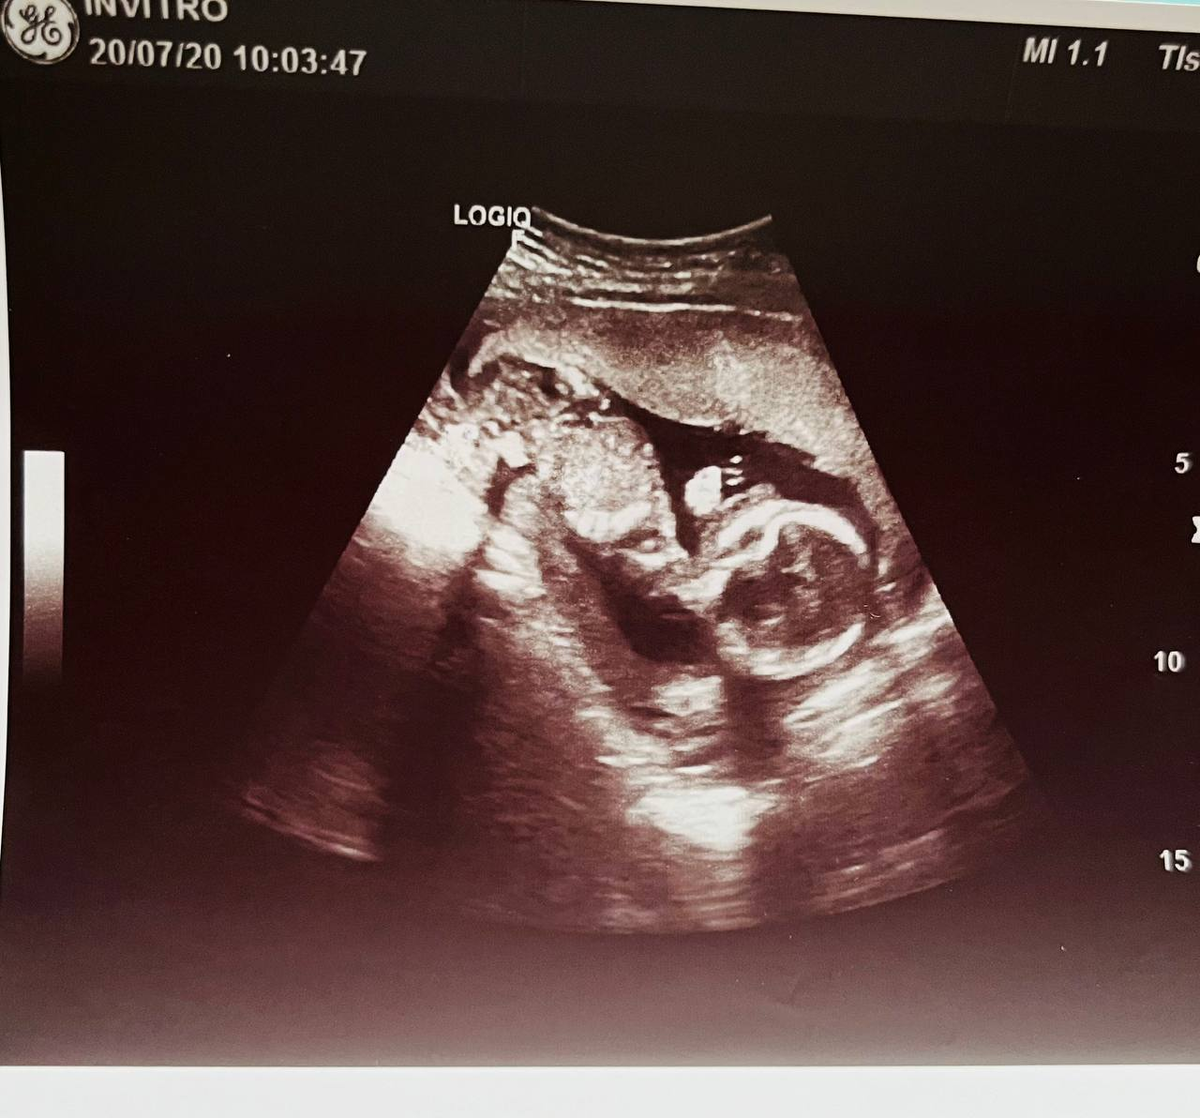

Сосательный рефлекс в утробе матери на УЗИ

При проведении ультразвукового исследовании плода мы видим постоянно один из самых ранних рефлексов ребёнка - сосательный рефлекс. Он как раз формируется, когда малыш находится еще в утробе матери. Ребенок тянет в рот все, что ему попадается: пуповину, свою ручку или ножку. Но чаще всего он сосет свой большой палец🙈

И придя с очередного приема гинеколога ЖК, я сделала сама себе УЗИ. Да попала в тот момент, когда моя дочь сосала большой палец☺️🙈

(Фото из личного архива)